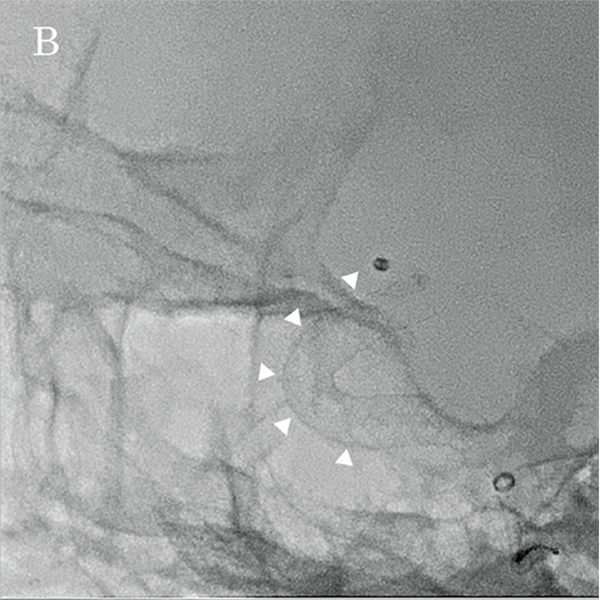

На основі цих вимірювань було обрано пристрій для емболізації Pipeline™ (PED) (4,75 мм × 16 мм; Medtronic, Японія), аневризму лікували, спостерігаючи за флюорографічними зображеннями детектора високої чіткості (мал. 5A та 5B). Пристрій було розгорнуто від C2 (біфуркація задньої сполучної артерії) до C4, а розгортання FD і стан кримпування материнської судини підтверджено Alpha CT (мал. 6A і 6B).

Малюнок 5B: Бічне флюороскопічне зображення, отримане за допомогою HD-детектора (3 дюйми) під час розміщення FD.